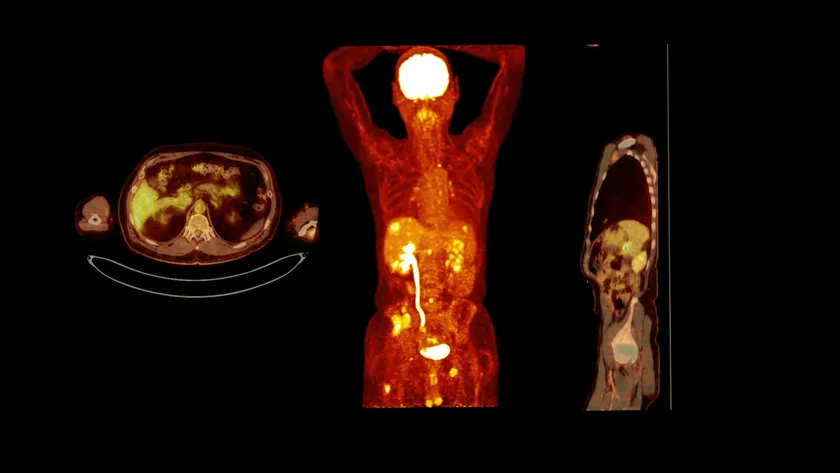

(4)同時にCT,MRI,PET-CTなどを依頼すると料金が安くなる、診断精度が上がること

従来の遠隔画像診断の場合、同一患者の異なる検査では、読影医が異なる場合があり、結果に一貫性がないことも多く、料金も別々に請求され割高でした。「画像診断ラウンジ」では、CT,MRI,PET-CTなどを同時に依頼することで料金が加速度的に割安になります。それぞれの画像を参照して総合的に診断するので、診断精度の向上にも繋がります。

PETCT